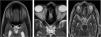

ResultsAmong the 20 specimens, we found two prefixed (10%), 10 normo-fixed (50%), and eight postfixed chiasms (40%). The mean interoptic angle was 81.03 (±17.41)⁰. Prefixed chiasms had angles in the range 115.36°–124.76 ° (mean 120.06 [±6.65]⁰), normo-fixed chiasm angles were between 83.11° and 97.53 ° (mean 86.07 [±6.73]⁰), and postfixed chiasms ranged between 53.01 ° and 78.71 ° (mean 69.20 [±9.13]⁰). The length of the right optic nerve ranged between 6.95 and 13.83 mm (mean 10.25 [±1.81] mm), and the length of the left between 7.25 and 12.51 mm (mean 10.40 [±1.47] mm). Obtuse angles indicated that the chiasm was prefixed, and acute angles were indicative of a postfixed chiasm. There was a strong negative correlation between optic nerve lengths and the interoptic angle; thus, as the length of the nerves increases, the interoptic angle becomes more acute.

ConclusionsWe have proposed a simple measurement of the optic nerve lengths and the angle between them to predict the relative location of the OC, which can be done easily on MRI.